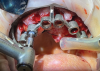

(3) Specialized drills permit osteotomy preparation and implant placement into vital cancellous bone, which is more vascular than cortical bone and can help to reduce bone loss.

Figure 3

(4.) Specialized drills permit osteotomy preparation and implant placement into vital cancellous bone, which is more vascular than cortical bone and can help to reduce bone loss.

Figure 4

Beyond hard-to-reach areas and the presence of metal, other factors, such as patient movement and the presence of saliva or blood can compromise the integrity of digital impressions, leading to inaccuracies with the placement and fit of the prosthesis. The dynamic nature of the mucosa (Figure 2) presents an additional layer of complexity because intraoral scanners may struggle to capture its anatomy with the same level of detail and accuracy as harder tissue structures, such as the teeth or keratinized tissue.6 The efficient management of soft tissue is crucial to the long-term success of implant therapy, impacting both the stability of restorations and the esthetic outcome. Failure to accurately capture detailed information about the soft tissue can compromise the success of implant restorations, potentially resulting in issues such as poor gingival health, peri-implantitis, and undesirable prosthetic emergence profiles.7 Ensuring proper bedding of keratinized tissue during the surgical phase can significantly enhance the success of intraoral scanning and implant-supported restorations. Furthermore, employing innovative drilling protocols and placing implants into adequate cancellous bone (Figure 3 and Figure 4) can alleviate strain on the overlying cortical bone, which typically exhibits less vascularity, and consequently, reduce alveolar remodeling, ultimately preventing bone loss around the crestal neck of the implant.